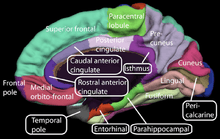

The OFC has been cytoarchitectonically and connectionally subdivided into a medial and a lateral portion. The medial portion has its strongest connections with the hippocampus and associated areas of the cingulate, retrosplenial and entorhinal cortices, anterior thalamus and septal diagonal band. The lateral portion can be further subdivided into three sectors. The most caudal sector is characterized by strong connections with the amygdala, midline thalamus, non-isocortical insula and temporal pole. The most anterior sector has more pronounced connections with the granular insula, association cortex, mediodorsal thalamus, inferior parietal lobule and dorsolateral PFC.[25]